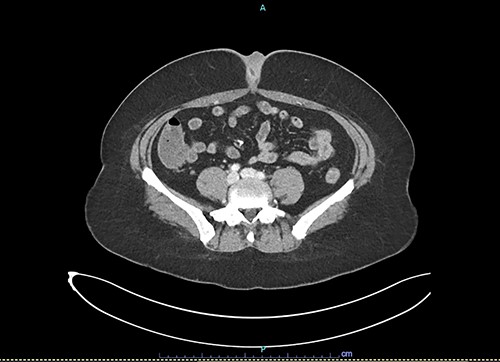

Blood tests revealed a normal white cell count of 8 x 109/L (reference range 4.0–12.0 x 109/L) and mildly elevated C-reactive protein of 8.7 mg/L (reference range < 5.0 mg/L). A computed-tomography (CT) scan revealed soft tissue thickening of the umbilicus of uncertain nature without intraperitoneal extension (Fig. 1).

Axial slice of contrast-enhanced CT scan showing umbilical soft tissue thickening and fluid-filled structure at presentation to emergency department.